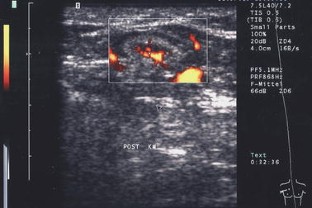

In 55 patients, 40 lymph nodes were correctly categorized as benign and 15 lymph nodes correctly as malignant. The most reliable criteria were shape and vascularization pattern. Intact hilar vessels and branching indicated benign enlargement, destruction of the hilum with vessels running peripherally along the capsule indicated metastatic destruction. Two benign lymph nodes were considered malignant (false positive).

B-mode ultrasound along with contrast-enhanced power Doppler ultrasound is an easy, cost-effective, and reliable tool for differentiation and categorization of enlarged superficial lymph nodes.